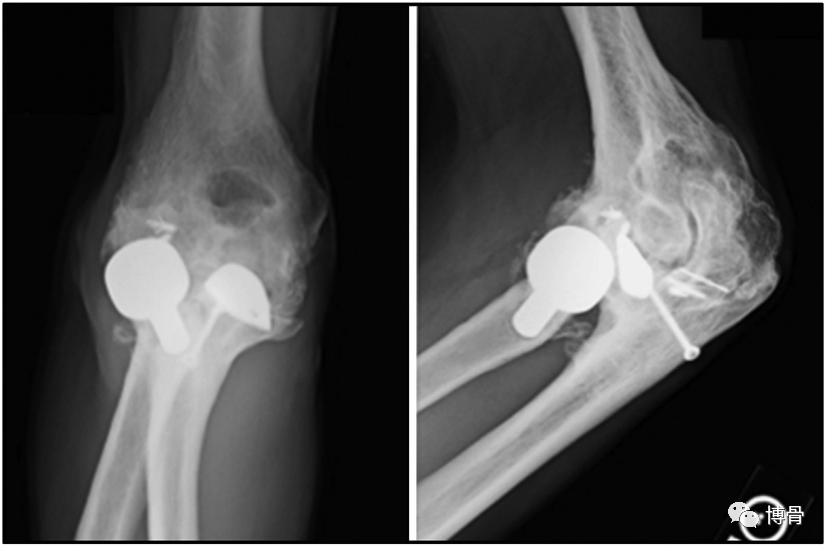

冠状突假体置换

冠状突假体置换术后11年,假体位置良好,但肘关节退变明显